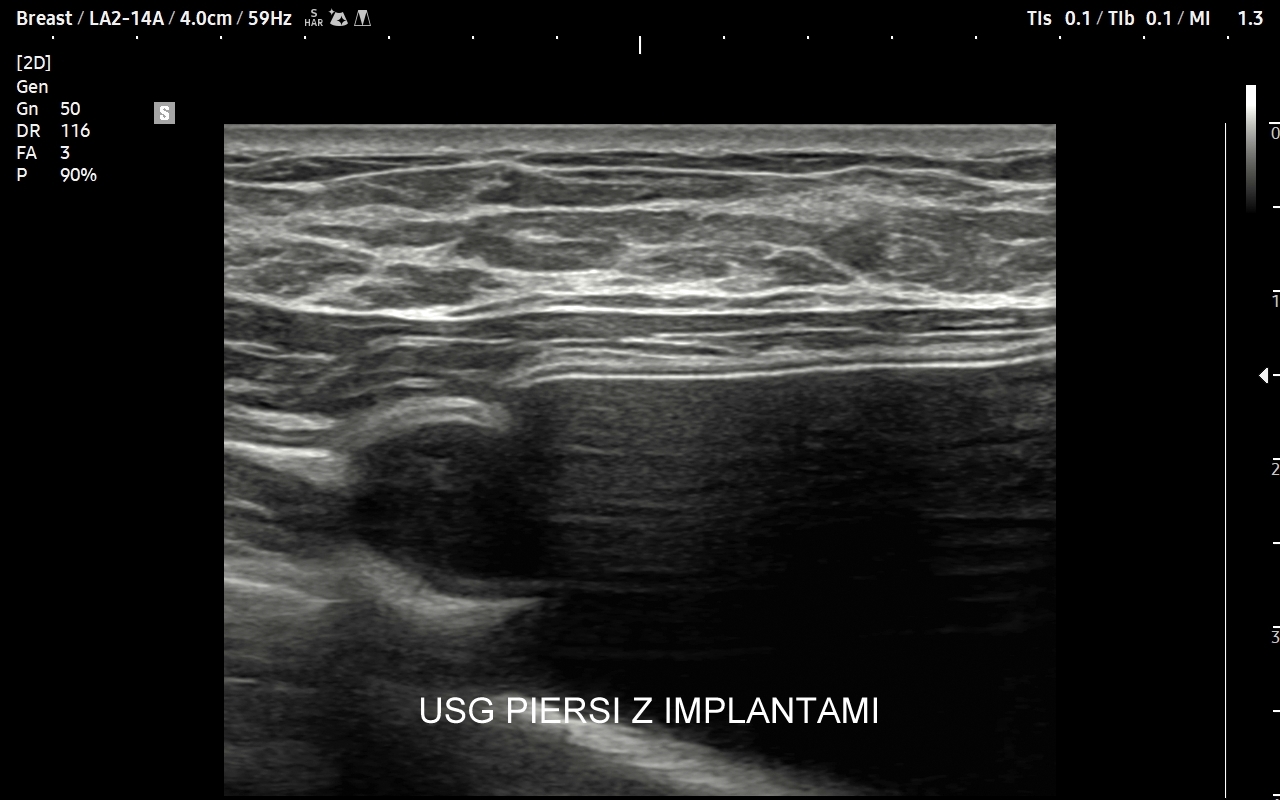

USG piersi z implantami

Badanie USG piersi z implantami jest szczególną procedurą diagnostyczną. Przeprowadza się ze wskazań wcześniej opisanych, jak w przypadku piersi bez implantów, ale także w schorzeniach ściśle związanych z implantem. Przykładami są powikłania chirurgiczne takie jak przemieszczenie się implantu, krwiak, ropne zapalenie tkanek wokół implantu, jego pęknięcie, a także wystąpienie chłoniaka BIA-ALCL (ang. breast implant associated anaplastic large cell lymphoma) jako odległego powikłania wszczepienia implantu piersi.